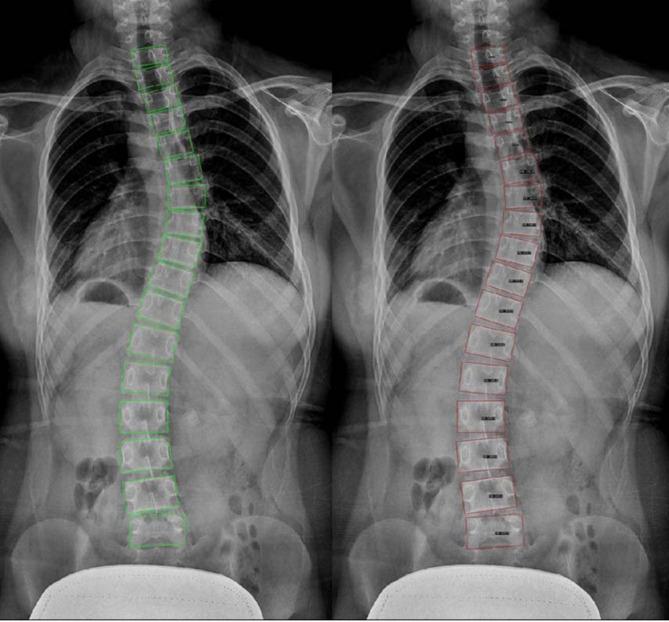

Accurate assessments of axial vertebral rotation (AVR) is essential for managing idiopathic scoliosis. The Nash-Moe classification method has been extensively used for AVR assessment; however, its subjective nature can lead to measurement variability. Therefore, herein, we propose an automated deep learning (DL) model for AVR assessment based on posteroanterior spinal radiographs. We develop a two-stage DL framework using the MMRotate toolbox and analyze 1080 posteroanterior spinal radiographs of patients aged 4-18 years. The framework comprises a vertebra detection model (864 training and 216 validation images) and a pedicle detection model (14,608 training and 3652 validation images). We improved the Nash-Moe classification method by implementing a 12-segment division system and width ratio metric for precise pedicle assessment. The vertebra and pedicle detection models achieved mean average precision values of 0.909 and 0.905, respectively. The overall classification accuracy was 0.74, with grade-specific performance between 0.70 and 1.00 for precision and 0.33 and 0.93 for recall across Grades 0-3. The proposed DL framework processed complete posteroanterior radiographs in < 5 s per case compared with conventional manual measurements (114 s per radiograph). The best performance was observed in mild to moderate rotation cases, with performance in severe rotation cases limited by insufficient data. The implementation of DL framework for the automated Nash-Moe classification method exhibited satisfactory accuracy and exceptional efficiency. However, this study is limited by low recall (0.33) for Grade 3 and the inability to classify Grade 4 towing to dataset constraints. Further validation using augmented datasets that include severe rotation cases is necessary.

准确评估椎体轴向旋转(AVR)对于特发性脊柱侧弯的治疗至关重要。Nash-Moe分类方法已被广泛用于AVR评估;然而,其主观性可能导致测量变异性。因此,在本文中,我们提出了一种基于脊柱后前位X线片的用于AVR评估的自动化深度学习(DL)模型。我们使用MMRotate工具箱开发了一个两阶段的DL框架,并分析了1080例4至18岁患者的脊柱后前位X线片。该框架包括一个椎体检测模型(864张训练图像和216张验证图像)和一个椎弓根检测模型(14608张训练图像和3652张验证图像)。我们通过实施一个12段划分系统和宽度比度量来改进Nash-Moe分类方法,以进行精确的椎弓根评估。椎体和椎弓根检测模型的平均精度值分别为0.909和0.905。总体分类准确率为0.74,0至3级的特定等级性能在精度方面为0.70至1.00,召回率方面为0.33至0.93。与传统手动测量(每张X线片114秒)相比,所提出的DL框架处理完整的脊柱后前位X线片的时间<5秒/例。在轻度至中度旋转病例中观察到最佳性能,重度旋转病例的性能受数据不足限制。用于自动化Nash-Moe分类方法的DL框架的实施表现出令人满意的准确性和卓越的效率。然而,本研究受到3级召回率低(0.33)以及由于数据集限制无法对4级进行分类的限制。有必要使用包括重度旋转病例的增强数据集进行进一步验证。